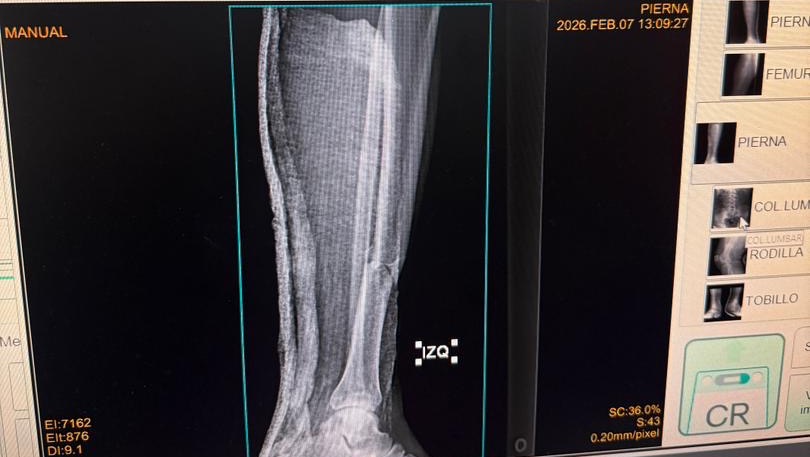

A sus 27 años, Jean Manuel Colella estaba cumpliendo una de sus metas más grandes: realizar sus prácticas universitarias en Barquisimeto, Venezuela. Sin embargo, la madrugada del 07 de febrero, su vida cambió en un segundo. Fue víctima de un terrible accidente automovilístico donde, lamentablemente, los responsables se dieron a la fuga, dejándolo atrás con heridas graves. Hoy, Jean Manuel enfrenta el reto más difícil de su vida. El accidente le causó múltiples fracturas en ambas piernas, siendo su pie derecho el más afectado. Para que él pueda volver a caminar, trabajar y terminar su carrera, necesita una cirugía de reconstrucción urgente. Cada granito de arena cuenta. Tu donación, por pequeña que parezca, es un paso más cerca de devolverle la movilidad a un joven que tiene todo un futuro por delante. ¡Ayúdanos a que Jean Manuel vuelva a ponerse de pie!

At the age of 27, Jean Manuel Colella was achieving one of his biggest goals: completing his university internship in Barquisimeto, Venezuela. However, in the early hours of February 7th, his life changed in an instant. He was the victim of a horrific car accident where, heartlessly, those responsible fled the scene, leaving him behind with severe injuries. Today, Jean Manuel faces the toughest challenge of his life. The accident caused multiple fractures in both legs, with his right foot being the most severely affected. In order for him to walk again, work, and finish his degree, he needs urgent reconstructive surgery. Every little bit helps. Your donation, no matter how small it may seem, is one step closer to restoring mobility to a young man with his whole future ahead of him. Help us get Jean Manuel back on his feet!